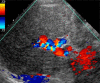

ARPKD/CHF is an inherited disease characterized by non-obstructive fusiform dilatation of the renal collecting ducts leading to enlarged spongiform kidneys and ductal plate malformation of the liver resulting in congenital hepatic fibrosis. ARPKD/CHF has a broad spectrum of clinical presentations involving the kidney and liver. Imaging plays an important role in the diagnosis and follow-up of ARPKD/CHF. Combined use of conventional and high-resolution US with MR cholangiography in ARPKD/CHF patients allows detailed definition of the extent of kidney and hepatobiliary manifestations without requiring ionizing radiation and contrast agents.